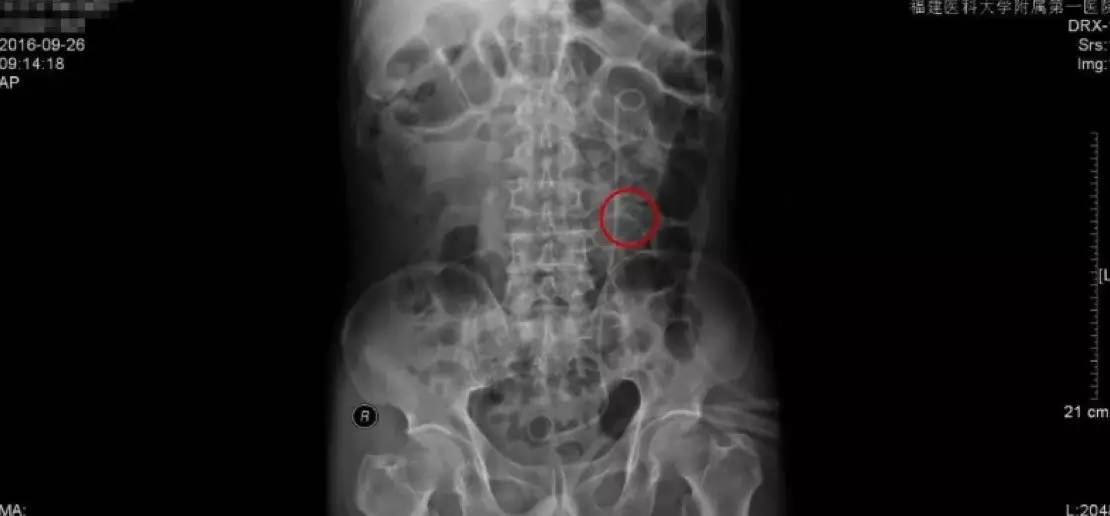

手术前KUB检查报告

手术后KUB检查报告

手术后的复查主要是通过拍KUB,通过与手术前KUB报告的直观对比,从图中可以看到,原来结石的地方,强化的结石已经消失了,左侧可以看到箭头指示的是一根手术后留置的双J管,这根管的目的是为了防止手术后输尿管狭窄黏连。

由于我们的手术是通过输尿管操作的,对输尿管粘膜不同程度有损伤,如果不留置双J管的话,术后容易造成输尿管黏连狭窄,输尿管最细的地方只有0.5cm,所以狭窄是手术后需要关注的并发症。